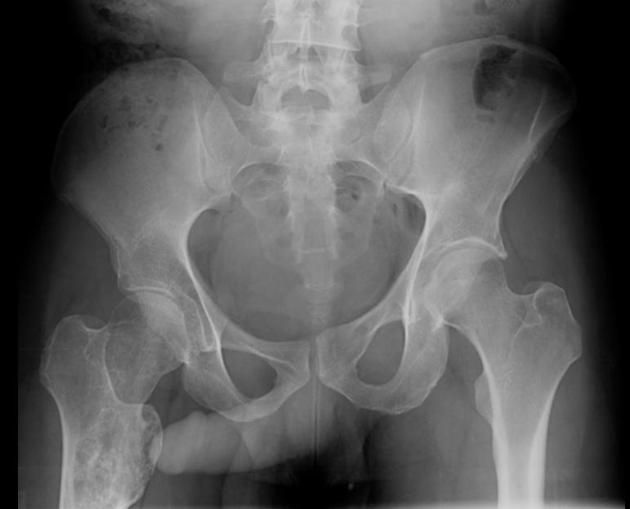

When I asked Google if, in an X-Ray of a hip and pelvis, the penis and testicles could be seen, it answered no. When I scrolled down, I saw about 400 comments stating otherwise. With pictures to prove it.

Now, to give Google some credit, it’s official answer was: “No, a standard X-ray of the hip and pelvis will not typically show the penis and testicles clearly, as they are soft tissues that are largely obscured by the surrounding bone structure; however, in some cases, with specific positioning and if the patient is very thin, faint outlines of the male genitalia might be visible on the image, but this is not reliable or intended for diagnosis.”

From Wikipedia: “The John Thomas sign, also known as the Throckmorton sign, is a slang or joke term used in the field of radiology. It refers to the position of a penis as it relates to pathology on an X-ray of a pelvis. When the penis (visible on the X-ray as a shadow) points towards the same side as a unilateral medical condition such as a broken bone, this is considered a ‘positive John Thomas sign,’ and if the shadow points to the other side, it is a ‘negative John Thomas sign.’”